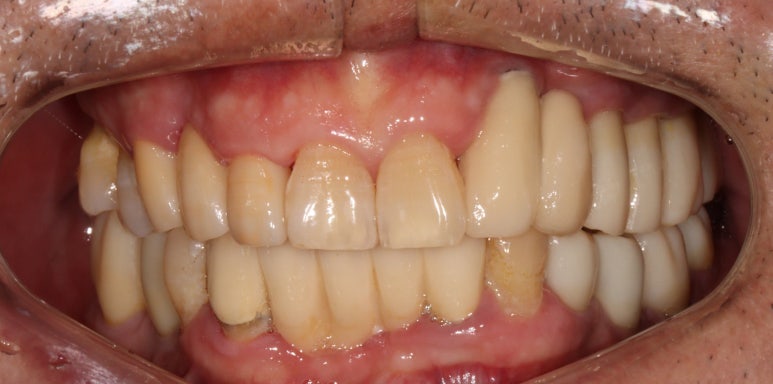

오른쪽 송곳니는 뽑고나서 앞니 지르코니아 브릿지로 권해드렸습니다.

이런 경우 저는 단호하게 앞니 임플란트 말고 앞니 브릿지를 권해드립니다.

그 이유가 앞에 나왔죠? 잇몸뼈를 너무 많이 잃어버린 상황에서 임플란트를 억지로 하면 임플란트 크라운이 너무 길어져 보기에도 안좋고 음식도 많이 끼고 결과적으로 임플란트 주위염에 시달릴 것이 뻔하기 때문이죠.

1주일 뒤에 제작된 앞니 지르코니아 브릿지입니다.

제가 봐도 좀 잘되었다고 감히 말할 정도로 완벽한 모습입니다....

사실 딱 보면 브릿지인지도 잘 모르겠네요...

바로 요기가 새로 제작한 지르코니아 앞니 브릿지입니다.

감쪽같은 앞니 치료 아니겠습니까!! 크... 제가 봐도 칭찬합니다.

입천장에서 바라보면 이제 가지런히 정렬되어있는 치아의 배열을 보실 수 있으실겁니다.

이번 환자분 같은 경우 위턱의 양쪽 송곳니가 한쪽은 앞니 지르코니아 브릿지로, 한쪽은 임플란트 브릿지로 치료가 된 특이한 상황이었습니다.

잇몸질환이 심한 환자분 대부분의 경우에서 앞니 임플란트보다 앞니 브릿지가 훨씬 예쁜 결과를 보여줍니다.

첫째로 적절한 치아길이를 가진 것 처럼 보이게 할 수 있고,

둘째로 치아와 치아 사이의 공간 (black triangle)을 최소화 할 수 있게 보철물을 제작할 수 있습니다.